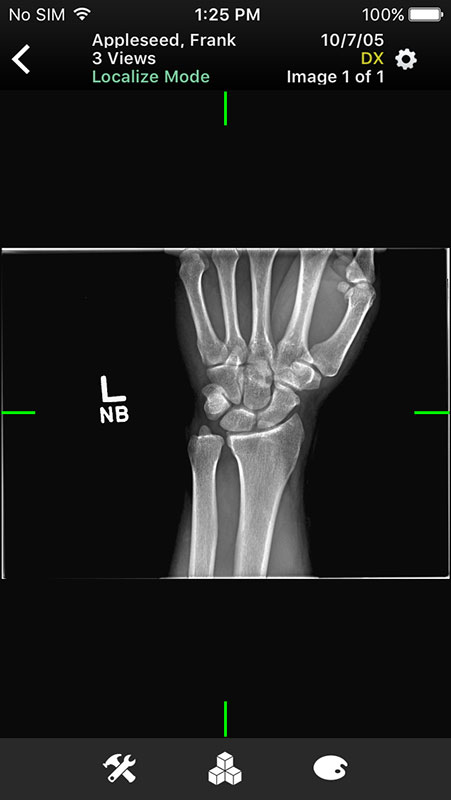

These sample images feature same imaginary patients and cases from the Mobile MIM app and contain X-ray, PETCT, MR, and ultrasound scans, alongside the name of the procedure.

Just like in Mobile MIM app, images open in multi-planar view allowing users to choose series depending on the type of imaging technique, add annotation, or measure the image.